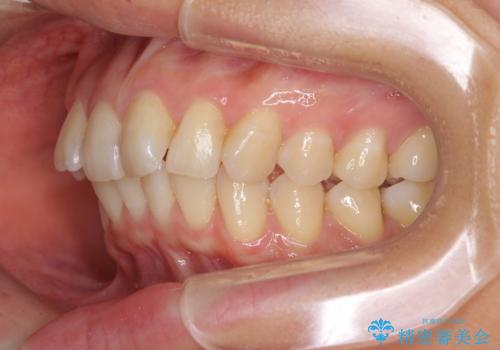

- 前歯の叢生と口元の閉じにくさを気にして来院された患者様です。

奥歯の咬み合わせを見ると、上顎が下顎に対して相対的に前方にありました。

口元の閉じにくさを改善するためには、上顎臼歯を後方に移動させた咬み合わせにする必要があります。

インビザライン単体で改善することも可能ですが、達成する可能性が高くないため、カリエールディスタライザーという補助装置を併用して、より確実性を上げることとしました。

奥歯の咬み合わせを改善しながら、並行してインビザラインで歯列を整えることとしました。